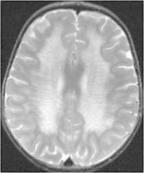

異染性腦白質營養不良癥狀

• 異染性腦白質營養不良

628健康網為您分享有關異染性腦白質營養不良的癥狀,異染性腦白質營養不良的治療方法,異染性腦白質營養不良的預防知識...